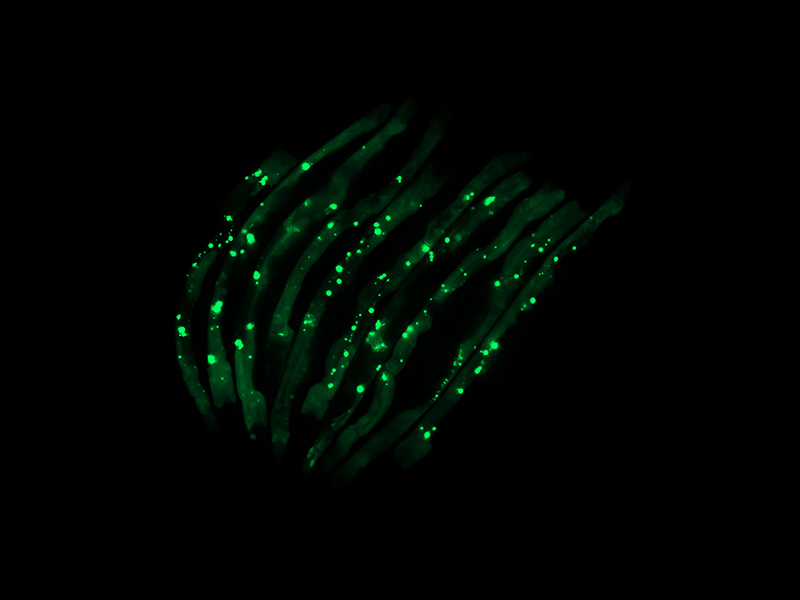

“That is, in fact, what we observed. We have a way of marking the aggregates so they glow green under the microscope. We saw that worms colonized by certain bacteria species were lit up with aggregates that were toxic to tissues, while those colonized by the control bacteria were not,” Czyz said. “This occurred not just in the intestinal tissues, where the bacteria are, but all over the worms’ bodies, in their muscles, nerves and even reproductive organs.”